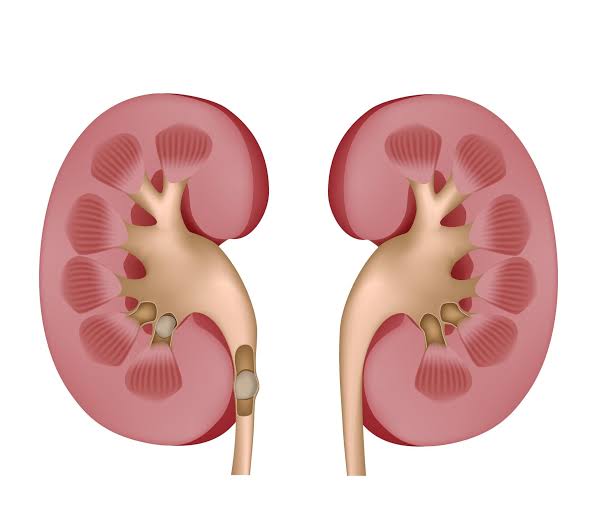

وأوضح أن الحصى عادة ما يتكون في تجويف الكلى، ولكن في حالة تصدعها تسقط داخل الحالب، مما يسبب آلاما حادة لا تحتمل.

وأشار إلى أن الحصى عادة ما يتكون من كالسيوم، وأيضا الفوسفور، بجانب الأوكسالات، وأيضا يتكون من حمض البولي، والكزونتين.

أوضح أخصائي في أمراض الكلى والمسالك البولية، تشخيص حصى الكلى، من خلال عدة عوامل، من حيث عمل اختبار إفراز الكلية للكمية من المعدن أو المواد التي تؤدي إلى تكوين الحصى، وأيضا من حيث حجم البول الذي يؤدي إلى تركيز المعادن والشوادر، وكذلك الفضلات.